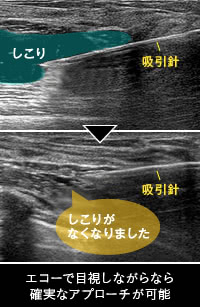

しこりを完全になくすためには、エコーでしこりを目視しながら確実に分解したり除去したりすることが必須条件。触診だけを頼りにした方法ではピンポイントなアプローチができないため、完全に除去することは難しく、しこりが消滅したかどうかも確認できないので、残ってしまうことが少なくありません。そもそも、脂肪注入豊胸のしこりに対する正しい治療法はしこりの性質によって異なります。そのため、エコー検査でしこりの種類をきちんと診断してから治療法を選択することが不可欠であるという当院の研究結果を、国際的な医学誌や国内の学会でも発表しています[1][2]